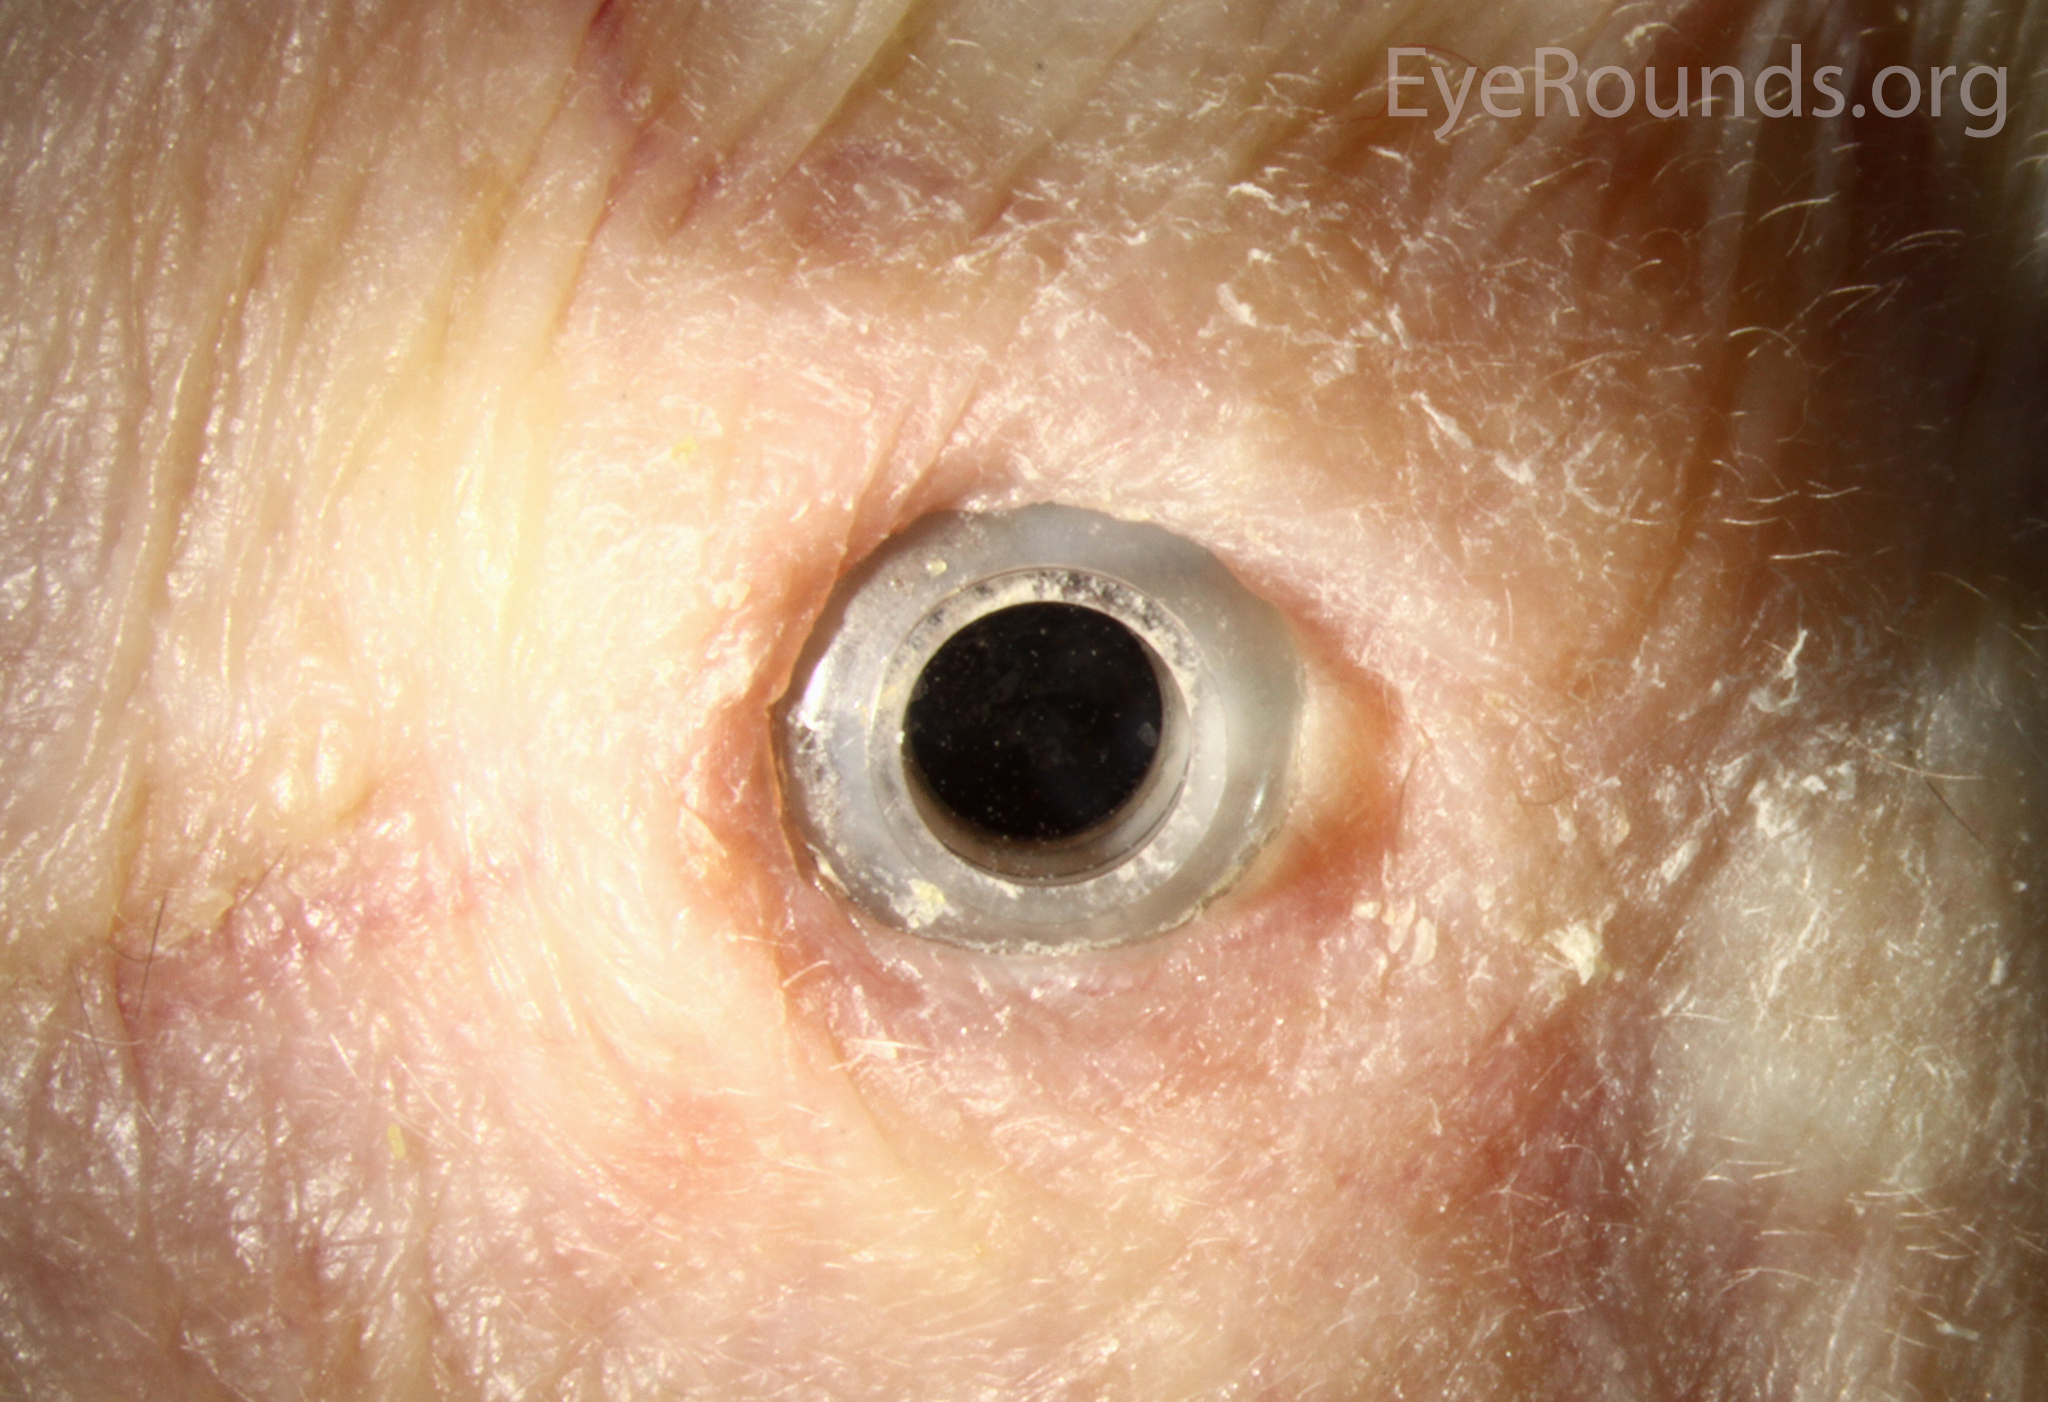

Keratoprosthesis implantation is a procedure that involves full-thickness removal of the cornea and replacement by an artificial cornea. The Boston Type I Keratoprosthesis is currently the most commonly used keratoprosthesis device in the US. It consists of a clear plastic polymethylmethacrylate (PMMA) optic and back plate sandwiched around a corneal graft and secured with a titanium locking ring (Figure 15). After the device is assembled, a partial-thickness trephination is performed on the host cornea. Full-thickness resection of the patient's cornea is then completed using curved corneal scissors. The keratoprosthesis is then secured to host tissue using interrupted or running sutures. Generally, patients who have a history of multiple failed PKs are candidates for a keratoprosthesis transplant. Other indications include severe keratitis or ocular surface disease resulting from limbal stem cell failure, such as Stevens-Johnson syndrome (Figure 16), ocular cicatricial pemphigoid, aniridia (Figure 17) and chemical injury (1, 13). The Boston Type II Keratoprosthesis is a similar device with a longer optic designed to extend through an opening made in the upper eyelid (Figure 19). It is indicated for the most severe cicatrizing ocular surface diseases.

KPro placement offers relatively fast visual rehabilitation. The devices are amenable for use in many situations in which other types of keratoplasty are not an option.

There is significant long-term risk of complications for those with a keratoprosthesis. Because the KPro is a foreign body, there is risk of infection or extrusion of the device. Post-operative glaucoma is common and intraocular pressure is difficult to evaluate as the hard optic makes traditional tonometry impossible. For this reason, glaucoma tube shunts are typically placed at the time of the corneal transplant at the University of Iowa. The Diaton is currently the preferred way to measure intraocular pressure in these patients in our institution. Patients can form retroprosthetic membranes requiring treatment with a Nd:YAG laser or surgical membranectomy (21).